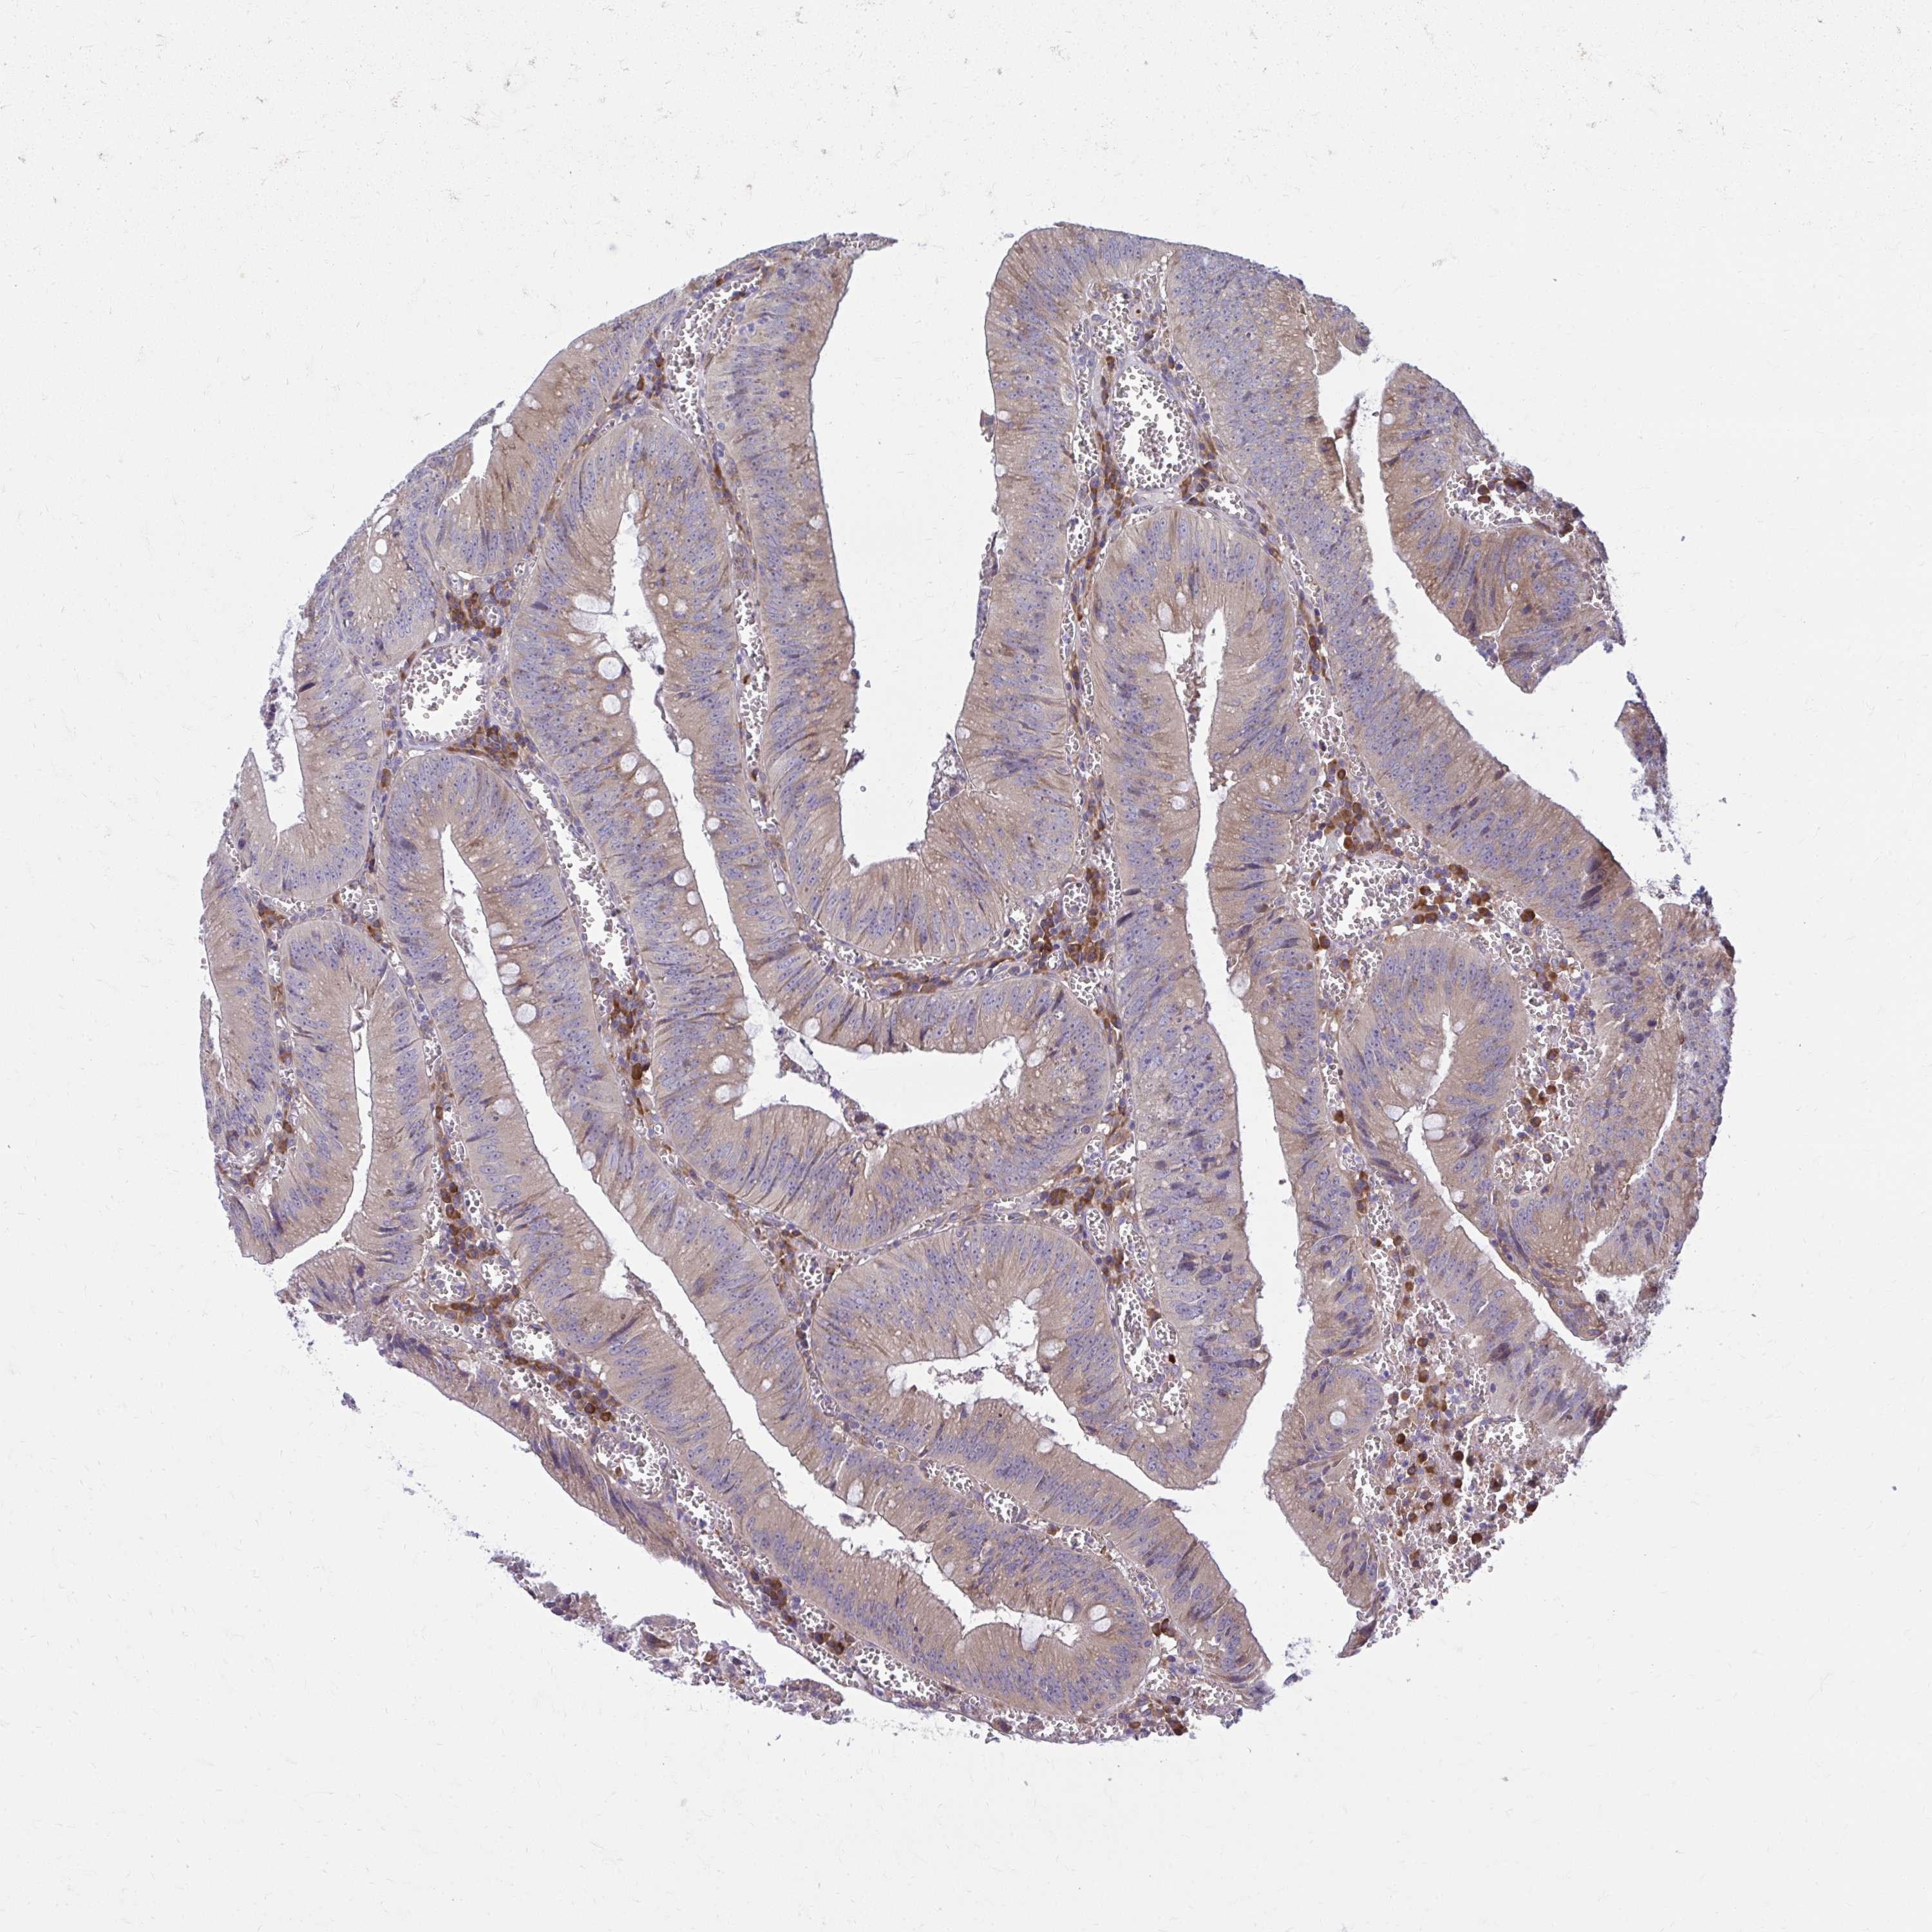

CANCER COLORECTAL CANCER Show tissue menu

Colorectal cancer

Human cancer

Colon adenocarcinoma